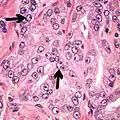

Adenocarcinoma with two mitoses in reactive epithelium.